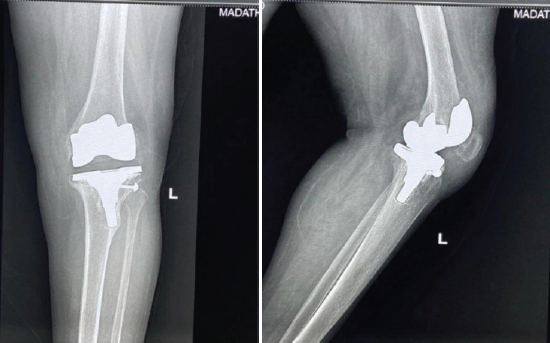

A 60-year-old female presented with pain, swelling, and a chronic discharging sinus over the anterior aspect of the left knee for 8 months following primary TKA performed elsewhere. She complained of difficulty in ambulation and recurrent episodes of fever. Clinical examination revealed a healed midline scar with an active sinus, valgus deformity of approximately 12°, and restricted knee movements (range: 10°–60°). Laboratory investigations showed elevated inflammatory markers (erythrocyte sedimentation rate [ESR]: 68 mm/h, C-reactive protein [CRP]: 42 mg/L). Plain radiographs (Fig. 1) demonstrated loosening of both femoral and tibial components with surrounding osteolysis. Joint aspiration and sinus tract culture grew methicillin-sensitive Staphylococcus aureus.

Figure 1: Weight-bearing radiographs showing loosening of both femoral and tibial components with surrounding osteolysis.